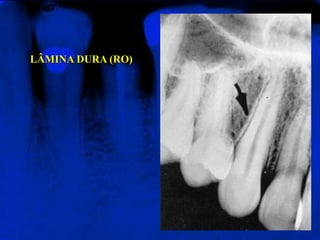

LÂMINA DURA (RO)

Representa a porção da parede do alvéolo onde se inserem

as extremidades externas das fibras periodontais. Apresenta-

se radiograficamente como uma linha radiopaca fina que se

continua com as cristas ósseas alveolares.

LÂMINA DURA (RO) Representaa porção da parede do alvéolo onde se inserem as extremidades externas das fibras periodontais. Apresenta- se radiograficamente como uma linha radiopaca fina que se continua com as cristas ósseas alveolares.